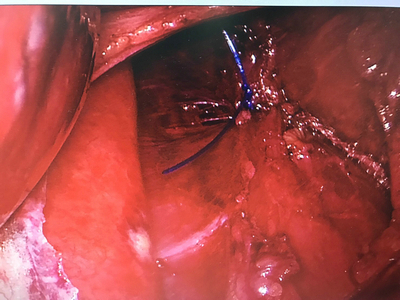

橫隔膜和食道的地方。身體的組織發生移位,食道裂孔往上移位,由橫隔膜發生裂孔而造成。 身體組織因為分隔不良而跑到有空隙的地方。是所有橫膈膜疝氣中最常見是一種退化性疾病,主要原因下食道括約肌的肌肉弱化,需特別注意年長者、肥胖與身材壯碩之病患有較高之發生率,往往只有5%較嚴重食道裂孔疝氣病患,外加上有胃食道逆流症,有上腹悶熱感及心灼熱、溢酸、吞嚥疼痛、甚至吞嚥困難;大部分95%病患只有輕微胸口悶痛、心灼熱感與食物停滯感之不適。 可分為兩種 1滑行性 2.食道旁 A.滑行性裂恐赫尼亞(Sliding hiatal hernia) : 食道和胃的交接處esophagogastric junction往上移動至橫隔膜上方,為鐘型的形狀。 徵狀不明顯,也許在心臟會有burnning的情況、或逆流的情況。 B.食道旁裂恐赫尼亞(paraesophageal or rolling hernia) : 一部份胃底部(gastric fundus)沿著食道旁往胸腔突出, 食道與胃的交接處並未位移 外科治療—腹腔鏡胃底折疊術(Laparoscopic Nissen's fundolpication):施行腹腔鏡微創手術,利用胃的底部部分來包繞遠端的食道,並修補隔疝氣的缺陷。手術的預期效果: 可改善90%病人「火燒心」的症狀,減少藥物使用。可治癒85%因GERD所引起的氣喘或呼吸症候。增進胃的排空:50%